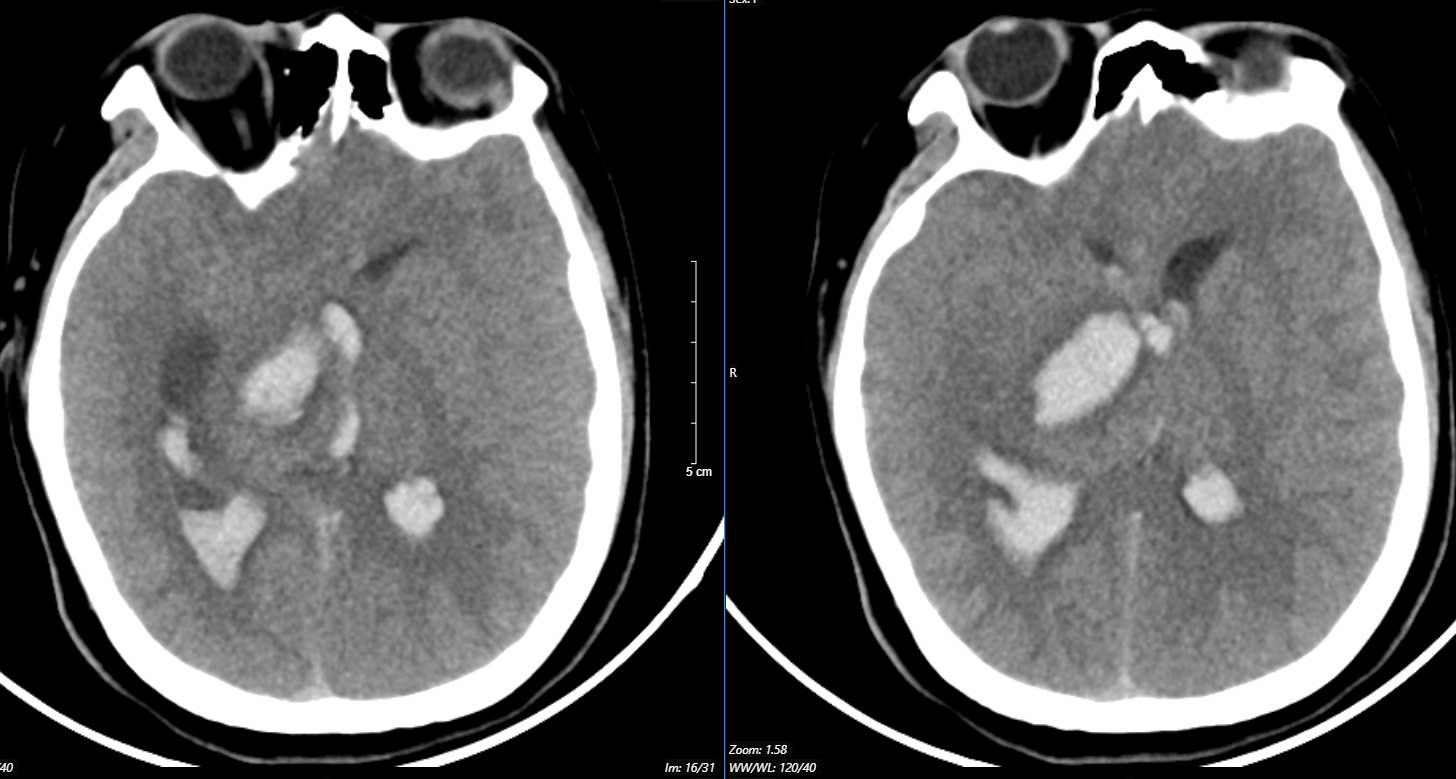

Bệnh nhân tới Bệnh viện Bạch Mai trong tình trạng hôn mê sâu, thở máy, giãn đồng tử bên phải. Kết quả chụp phim MSCT mạch máu não cho thấy bệnh nhân bị chảy máu não đồi thị - não thất do vỡ khối dị dạng động - tĩnh mạch não (AVM) biến chứng giãn não thất cấp. Bệnh nhân bị rối loạn thân nhiệt, sốt cao liên tục 39 - 40 độ C.

Một trường hợp khác là bệnh nhân 19 tuổi đến Trung tâm Đột quỵ, Bệnh viện Bạch Mai trong tình trạng co giật, hôn mê sâu, thở máy qua ống nội khí quản, liệt tứ chi. Kết quả chụp phim MSCT mạch não của bệnh nhân có hình ảnh chảy máu não thùy đỉnh chẩm bên trái và não thất - phù não lan toả do vỡ ổ dị dạng AVM thuỳ đỉnh chẩm trái. Bệnh nhân đã được phẫu thuật hút khối máu tụ và lấy ổ dị dạng mạch não.

Bệnh nhân được chuyển tới Bệnh viện Bạch Mai trong tình trạng ý thức hôn mê, thở máy, đồng tử bên phải giãn 4mm, tụt huyết áp, duy trì vận mạch. Ảnh chụp MSCT mạch máu não cho thấy bệnh nhân bị chảy máu não thuỳ đỉnh phải, chảy máu não thất do vỡ khối AVM.